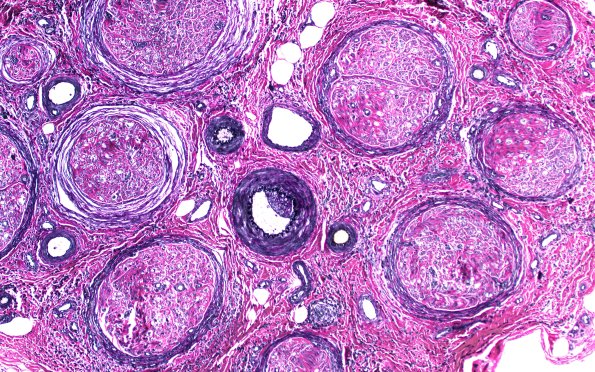

Washington University Experience | PERIPHERAL NEUROPATHY | 9B PERINEURITIS & PERINEURIAL PATHOLOGY | 1C1 Epineuritis & Perineuritis (Case 1) Immune checkpoint VVG 1B

1C1,2 This elastin stain demonstrates expansion of the perineuria of multiple fascicles and does not show large vessel vasculitis.